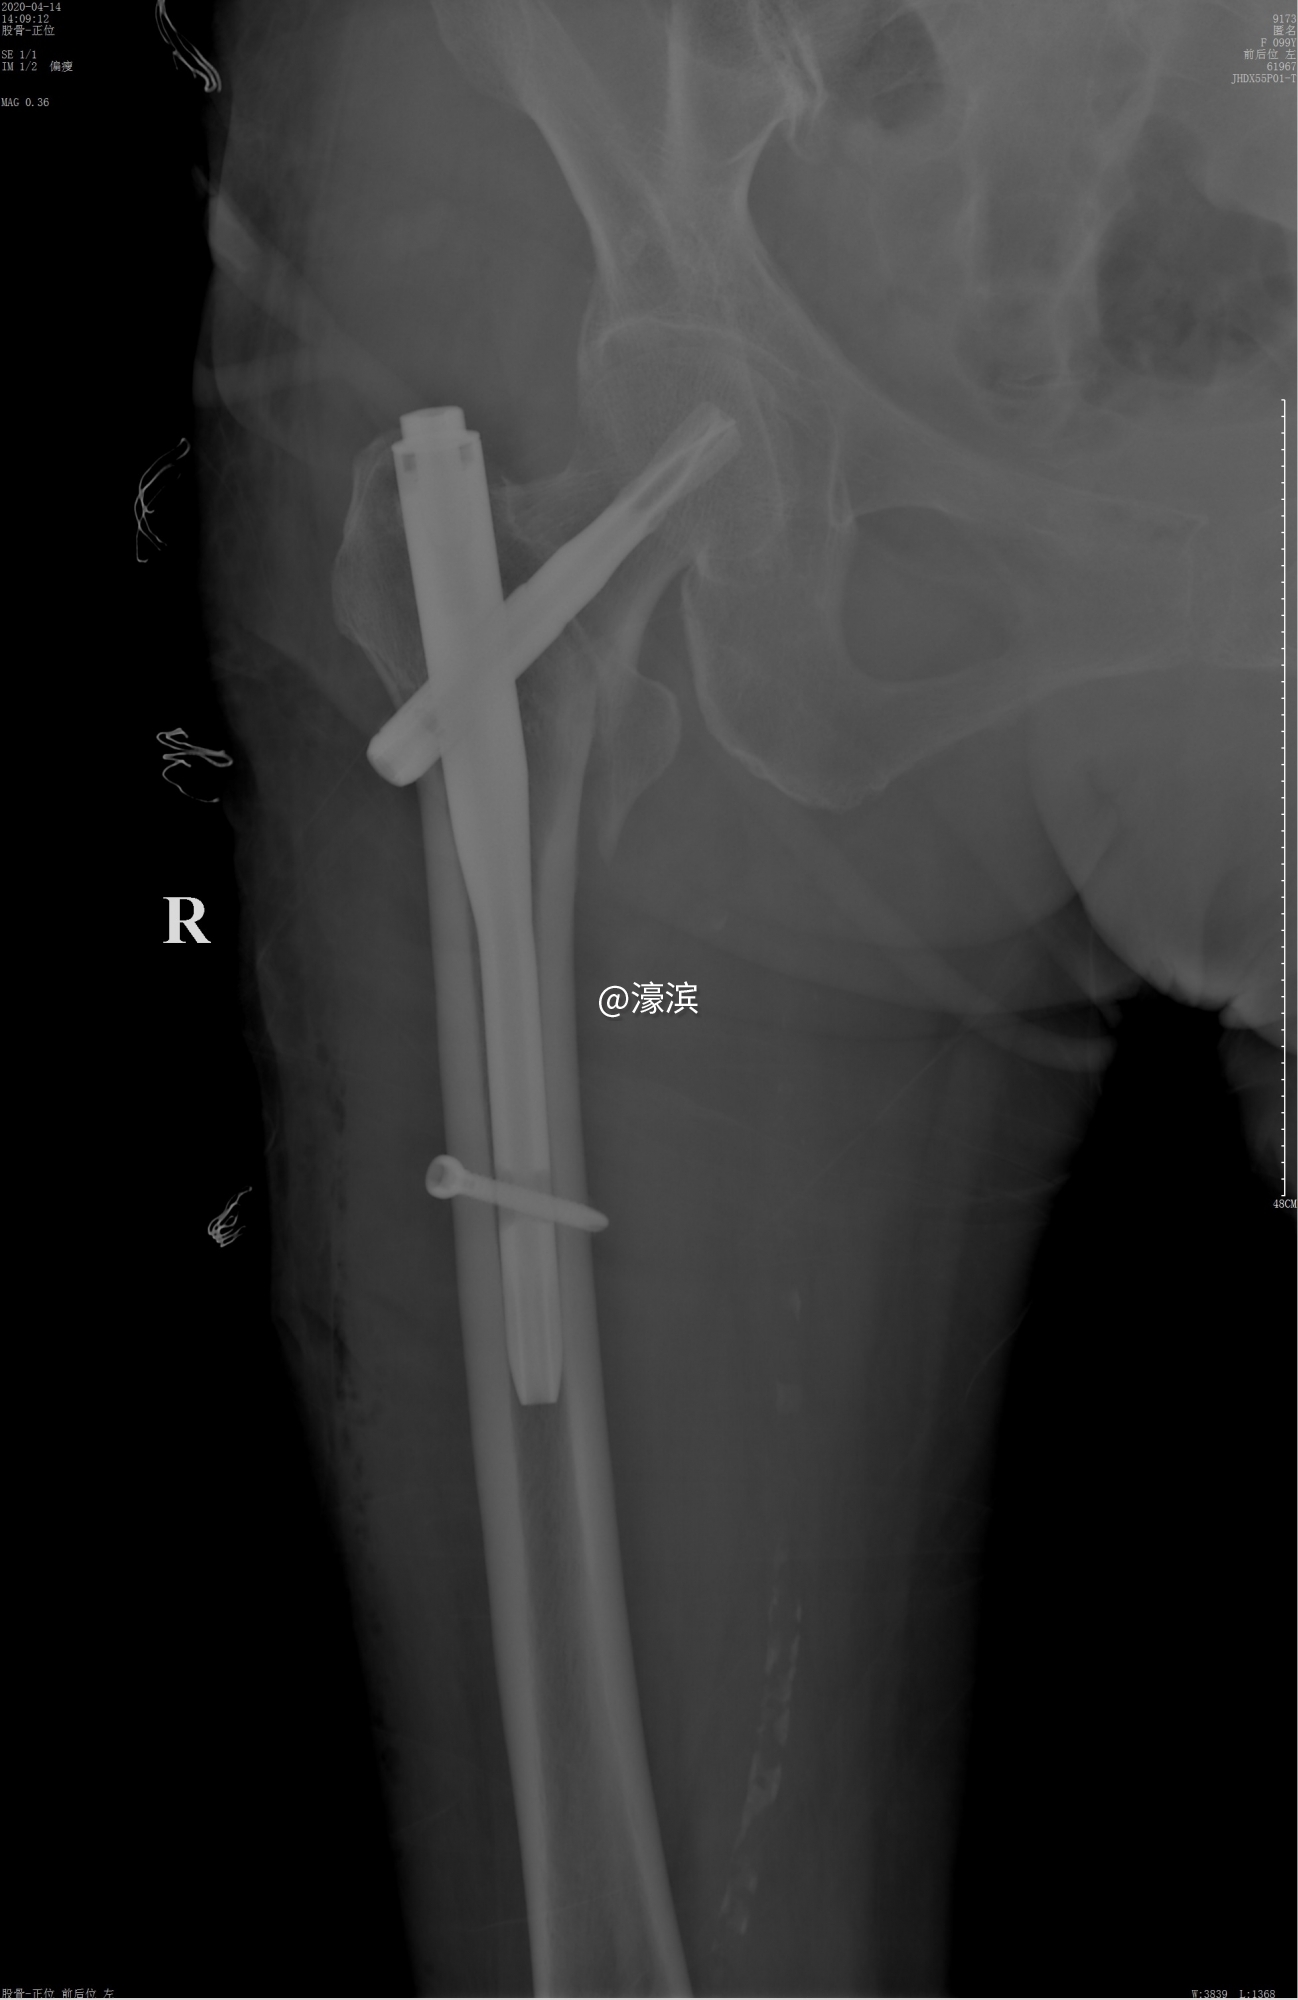

经过缜密的术前检查及准备后,在姚奶奶入院的第二天,创伤骨科专家团队就为姚奶奶施行了“右侧股骨粗隆间骨折闭合复位内固定术”,手术过程顺利,手术时间为1个小时10分钟。术后在患者及医护人员的共同努力下取得了良好的康复效果,患者及家属也对此次治疗效果十分满意。近年来,我院创伤骨科团队已经成功为多名高龄老人实施各类骨折手术,在对高龄骨折患者的处理方面积累了丰厚的治疗经验。

9173_61967_00001_00001_1_W3839L1368.JPG

术后拍片